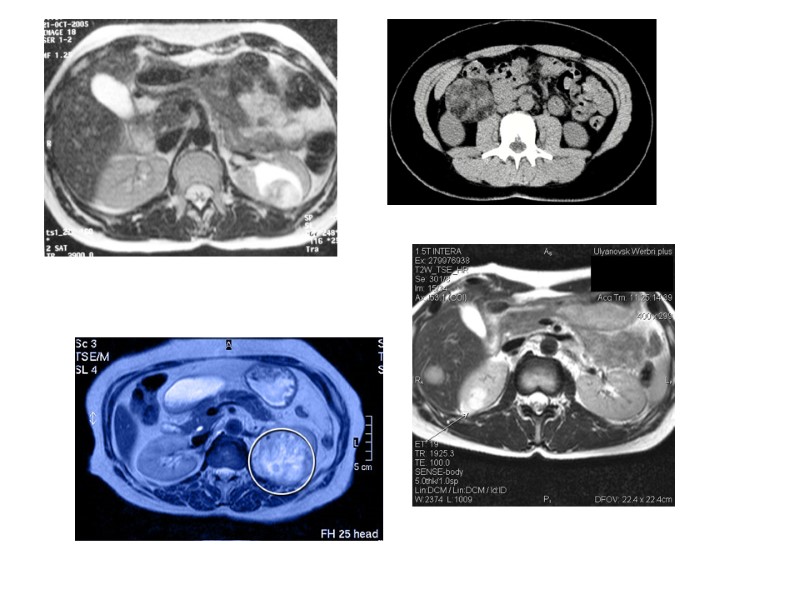

КТ

Диагностика. Общепризнанным скриннинг-тестом в выявлении обьемных образований почки является УЗИ. Если при УЗИ выявляется образование в почке, проводится расширенное обследование, которое включает исследование крови и мочи, КТ с "усилением", выделительная урография, остеосцинтиграфия, УЗИ органов брюшной полости, ангиография (по показаниям).

Для оценки степени распространенности опухолевого процесса рекомендуется проведение: КТ легких (при наличии опухолевого поражения почки в сочетании с опухолевым тромбозом нижней полой вены); МРТ брюшной полости - для оценки степени протяженности тромба при наличии опухолевого поражения почки в сочетании с опухолевым тромбозом нижней полой вены; Остеосцинтиграфия.